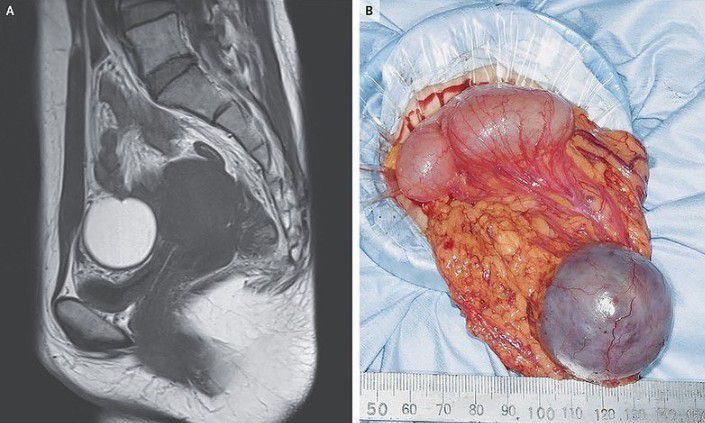

A 37 year old woman in the ER presented with excruciating menstral cramps in the lower abdomin. Laproscopy was performed and omental endometriosis was diagnosed. Endometriosis of the omentum is extremely rare and may originate from metastasis or metaplasia. Reported by: https://www.instagram.com/p/CMKCQmXB9Un/?igshid=1x5en93zk3hi3